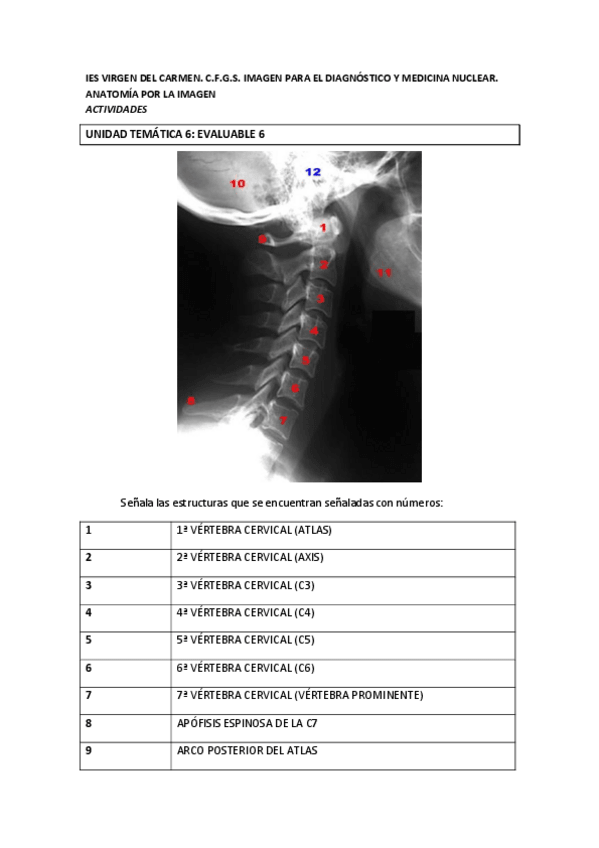

ACTIVIDADES EVALUABLES

He publicado nuevos apuntes de Anatomía por la imagen: ACTIVIDADES EVALUABLES

ACTIVIDADES ANATOMÍA

He publicado nuevos apuntes de Anatomía por la imagen: ACTIVIDADES ANATOMÍA